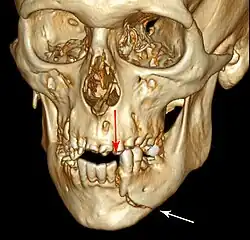

![]() | |

| 3D computed tomographic image of a mandible fracture in two places. One is a displaced right angle fracture and the other is a left parasymphyseal fracture. | |

Computed tomography

Computed tomography is the most sensitive and specific of the imaging techniques. The facial bones can be visualized as slices through the skeletal in either the axial, coronal or sagittal planes. Images can be reconstructed into a 3-dimensional view, to give a better sense of the displacement of various fragments. 3D reconstruction, however, can mask smaller fractures owing to volume averaging, scatter artifact and surrounding structures simply blocking the view of underlying areas.

3D CT reconstruction of mandible fracture, white arrow marks fracture, red arrow marks moderate displacement and open bite -